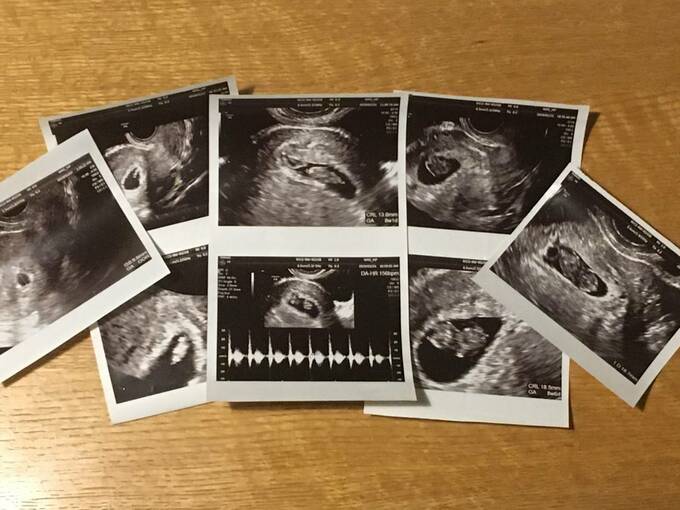

20代で3回流産、「女性として劣っている」とうつに。不育症の実態とは 記事に戻る スクロールで次の画像 (画像 1/5) この記事を読む 3回にわたる流産手術の同意書(ASCAさんご提供) (画像 2/5) この記事を読む ASCAさん (画像 3/5) この記事を読む 職場の同僚の妊娠もまた追い込んでいくように(※写真はイメージです) (画像 4/5) この記事を読む 3回目の妊娠時のエコー写真。右2枚の時点では心拍停止していたそう(ASCAさんご提供) (画像 5/5) この記事を読む 流産を繰り返し、妊娠するのが怖くなったという女性も多いといいます(※写真はイメージです)